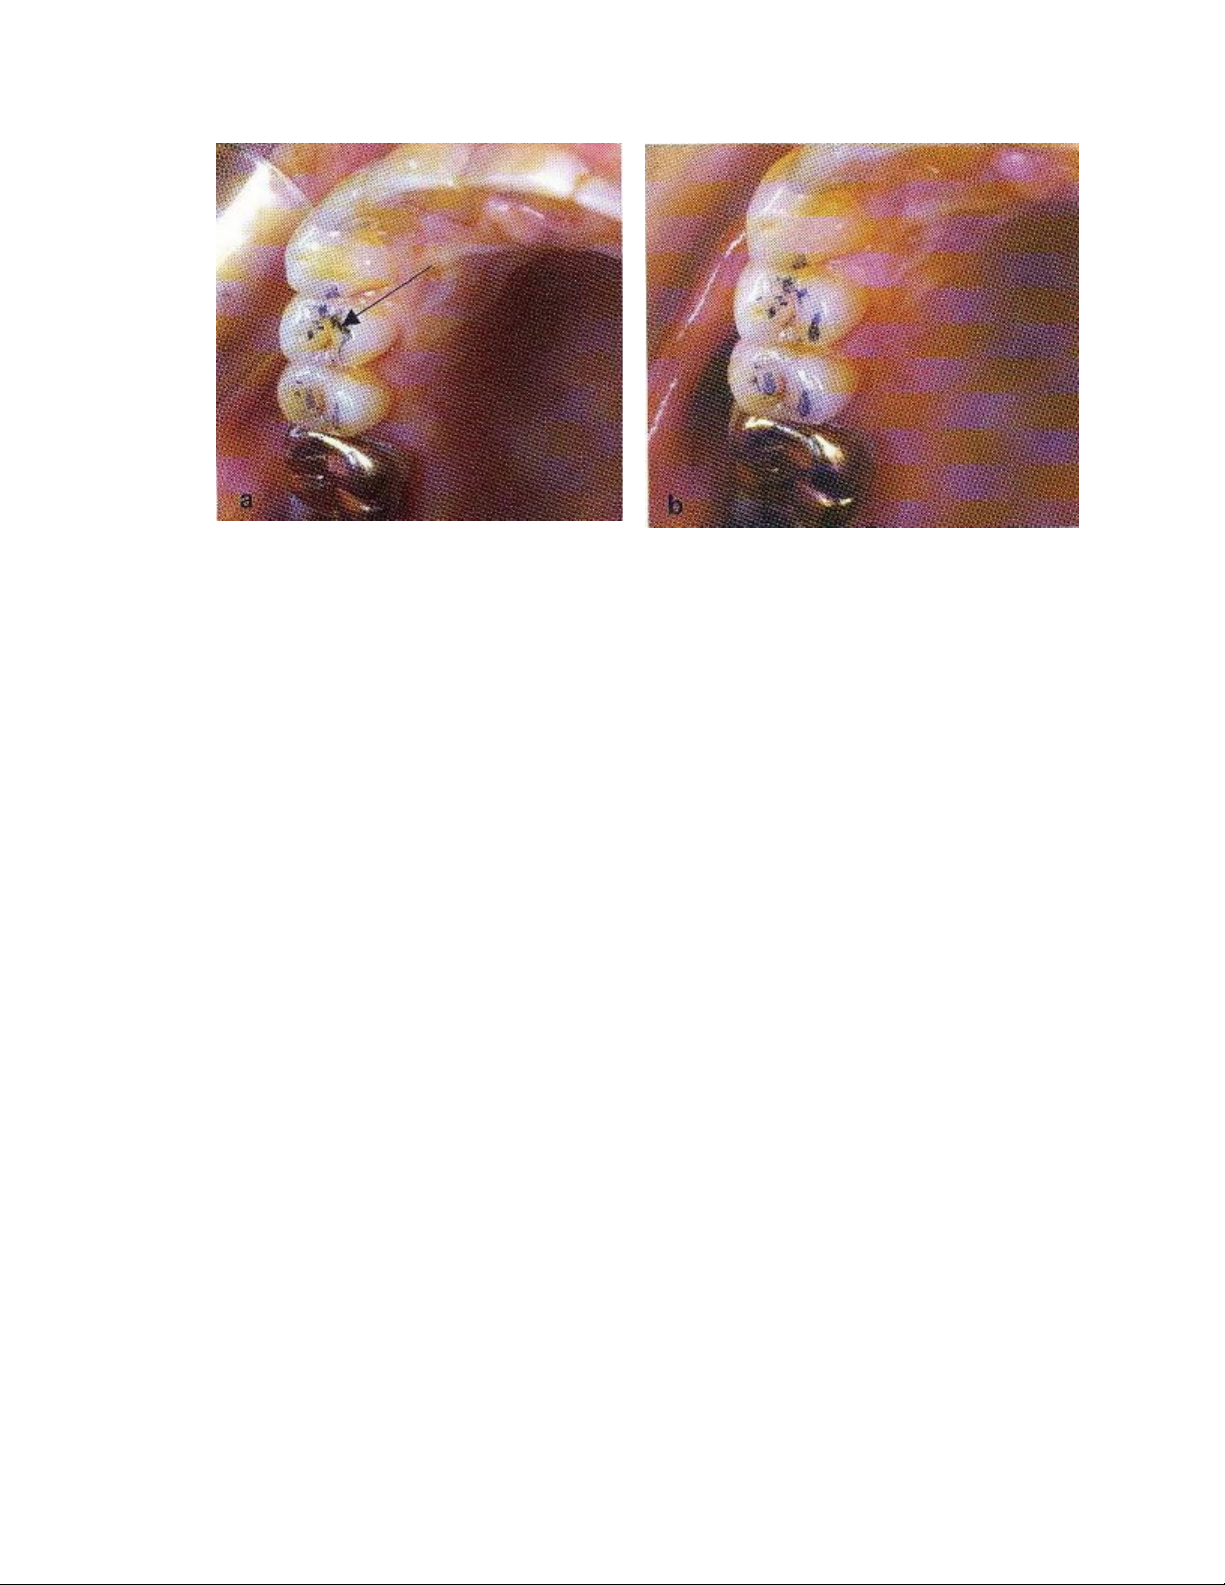

Hình : Các dấu cắn

Hình: Mài bớt Hình: Đắp thêm

Mức độ chạm ở khớp cắn chạm múi

tối đa bị ảnh hưởng vì có điểm

chạm sớm ở R14.

Điểm chạm sớm bị loại bỏ, các điểm

chạm ở khớp cắn chạm múi tối đa rõ

hơn.